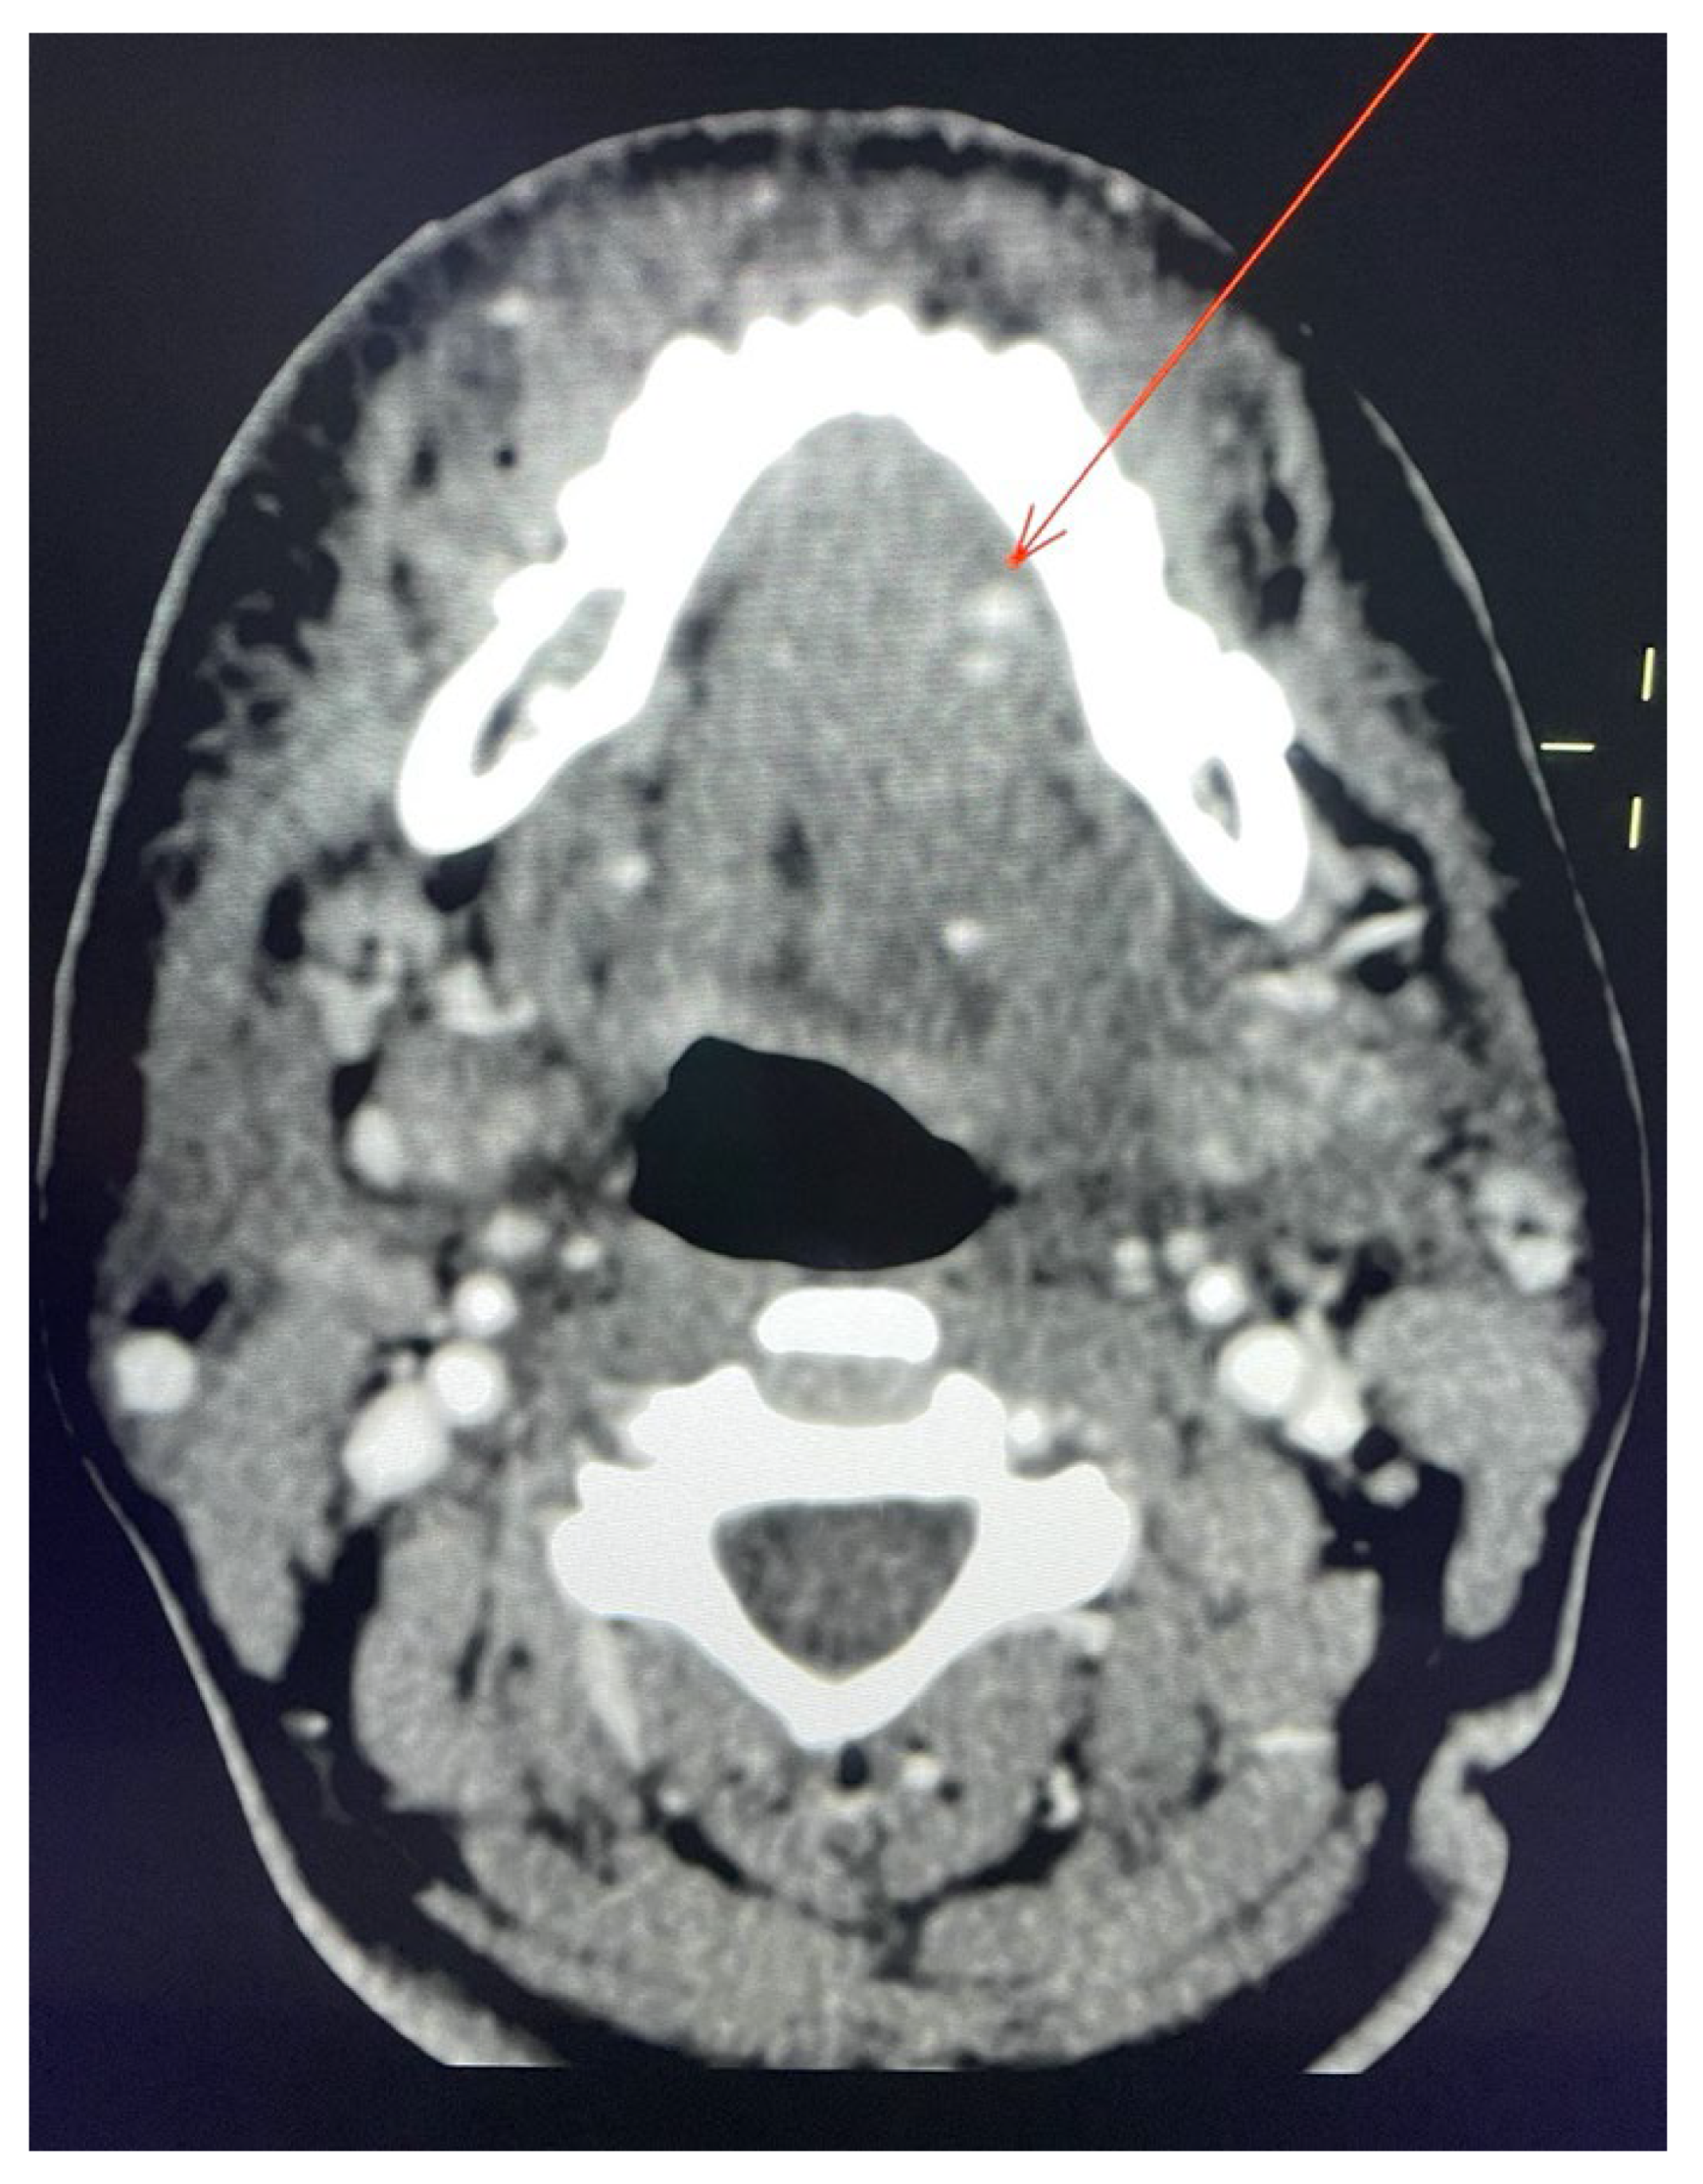

2. Case Report